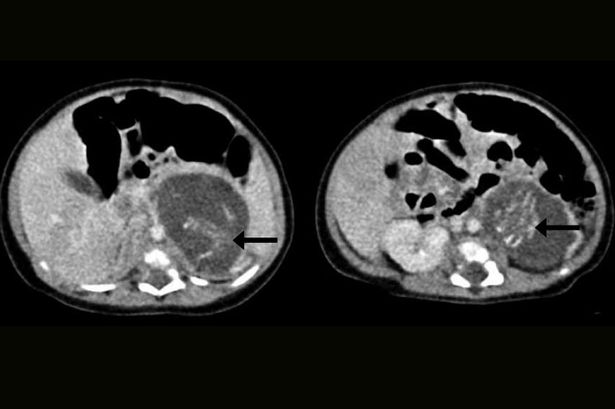

這名小女嬰出生才3個星期,之後卻被醫院檢查出她體內居然還有一對雙胞胎!香港的伊利沙伯醫院趕緊決定動手術將女嬰體內的胚胎移除。

女嬰體內的雙胞胎約成形了8到10週,已經有腿、手、脊椎、肋骨和腸子,也已經被皮膚包裹著,分別中14.2克和9.3克,也已經發展出了各自的臍帶。後來的胚胎移除手術相當成功,小女嬰在術後8天就出院了。